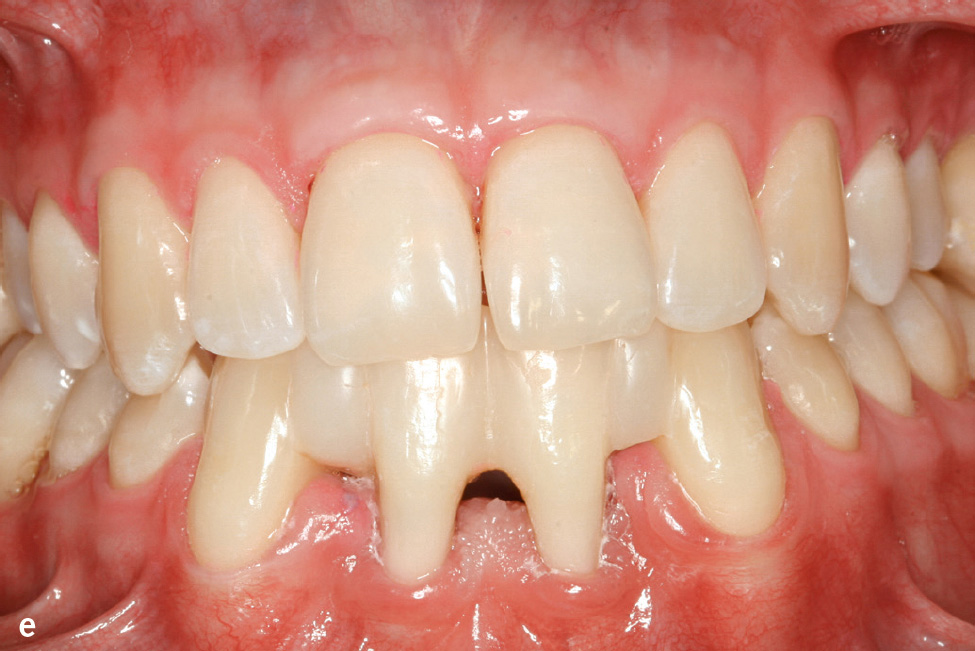

Die Therapie der Hautveränderungen erfolgt zum Teil mit oralen Retinoiden, aber auch urathaltigen Salben. Eine erfolgreiche Therapie der Parodontitis ist möglich. Der Erfolg scheint von verschiedenen Faktoren abzuhängen: möglichst frühzeitiger Beginn (ggf. schon im Milchgebiss), Elimination von A. actinomycetemcomitans und engmaschige professionelle Nachsorge (Abb. 1e und f)7.

Abb.1e und f e) Klinische Ansicht im Alter von 22 Jahren; 14 Jahre nach nichtchirurgischer antiinfektiöser Therapie mit unterstützender Gabe von Amoxicillin und Metronidazol und anschließender unterstützender Parodontitistherapie anfänglich alle 2, später alle 3 Monate; f) Panoramaschichtaufnahme zu Abb. 1e.